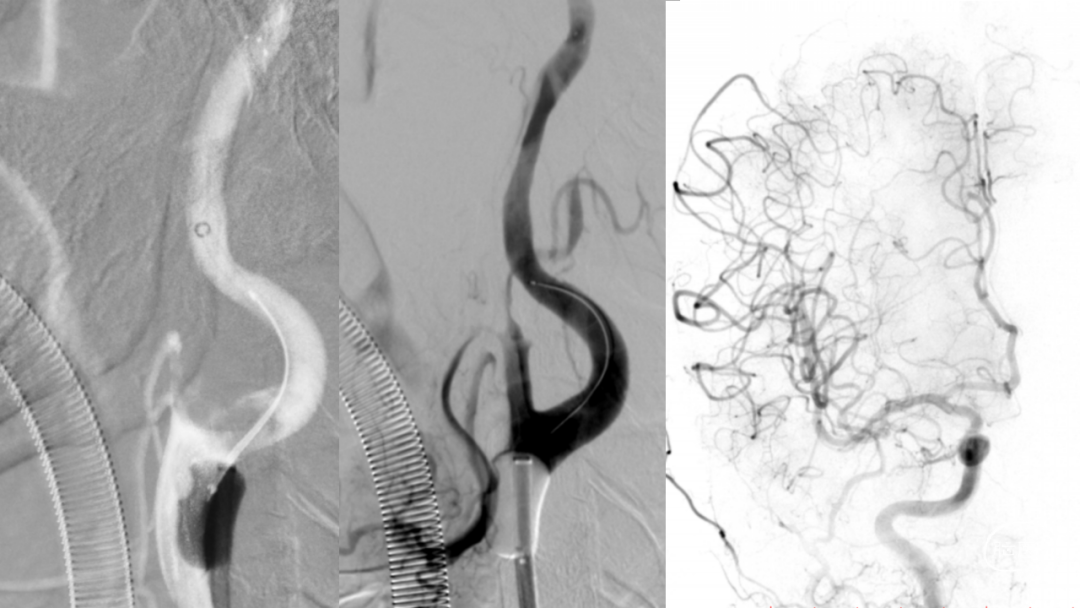

取之有道·第54期|李子付:Flowgate2取栓应用

看李子付解“取之有道”

滑动浏览更多内容